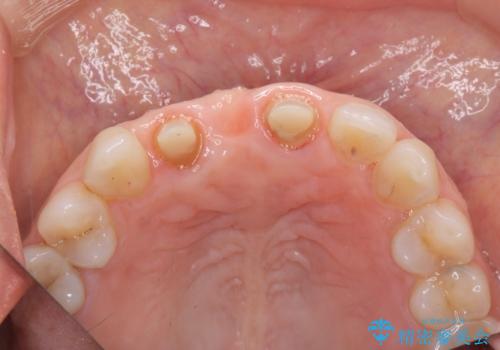

- 前歯のブリッジがすぐに外れる、歯ぐきが腫れている、見た目を良くしたい、と希望され来院されました。

現在装着されているブリッジを除去したところ、歯ぐきよりも上に存在する歯質(縁上歯質)が少なく、土台の形態の悪さや不適合などさまざまな問題があります。

根管治療を行ったのち、歯周外科を行うことで、欠損部の歯ぐきの厚みを出し、縁上歯質を獲得することで、長期的な予後の見込めるブリッジを製作できる環境を整備していきます。